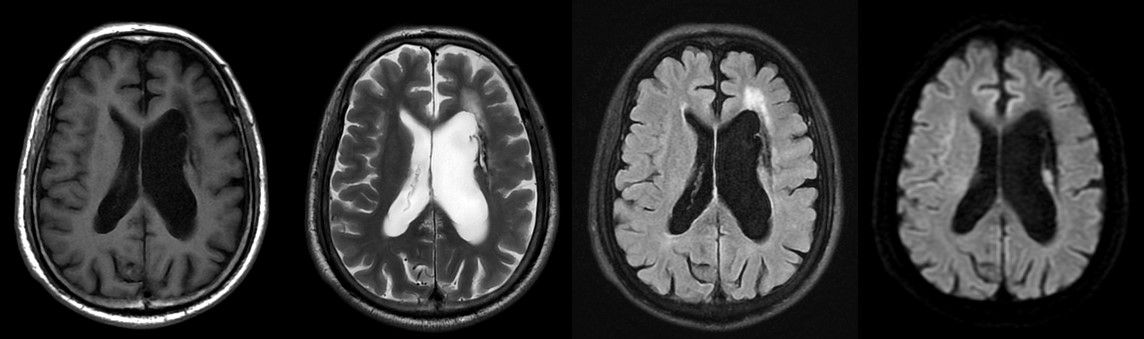

患者头颅MRA显示右侧颈内动脉及大脑中动脉完全闭塞,左侧颈内动脉狭窄,大脑中动脉未显影。立即往下扫描了颈部 MRA,颈部MRA显示右侧颈内动脉闭塞(绿箭),并在右侧颈外动脉多出了一个分支延伸至颅内(红箭),左侧颈内管腔狭窄(黄箭)。如此大面积的血管未显影,DWI上却未见新发病灶,病因是什么呢?

大部分影像科可能这时都会让患者回科室,把疑问留给临床医生琢磨了。但我院影像中心本着精准医学,精准影像先行的宗旨,不折腾患者来回跑,尽量一次折腾明白,继续扫描不打药灌注3D ASL:

3D ASL PLD=1.5s显示双侧大脑灌注相对减低,PLD=2.5s双侧大脑灌注恢复,说明存在灌注代偿,且右侧顶枕叶呈现高灌。

3D ASL为我们解答了为何患者血管大面积不显影,DWI上没有新发病灶,综合PLD=1.5s和2.5s来看患者虽然双侧大脑中动脉和大脑前动脉闭塞,但有灌注代偿,并未影响大脑供血;右侧顶枕叶呈现高灌,也印证了在TOF MRA上看到的右侧枕叶粗大的侧枝血管有代偿供血。到这一步基本解答我们的疑问,或许我们还需要一些直接的征象来证明我们的判断。SilenZ MRA(静音血管)也许能让我们看到更多的信息:

大范围基于3D ASL和ZTE的SilenZ MRA显示右侧颈外出现一支大的侧枝血管,供应右侧大脑,左侧颈内颅内段末端出现小的侧枝血管,且能看到Willis环周围许多细小的血管。

结合前面3D ASL和SilenZ MRA的征象,能想到烟雾病了,后询问得知患者有烟雾病家族史,遂入院进行相应治疗。